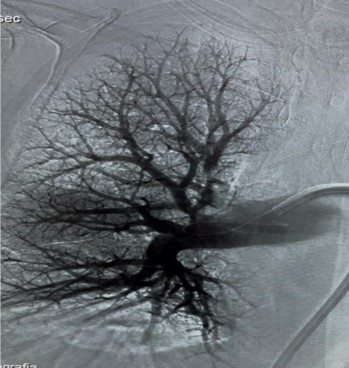

Usually, access was gained in the right femoral vein, and a 16-F, 65-cm Gore DrySeal sheath (Gore & Associates) was introduced into the vasculature and placed in the right or left main pulmonary artery (PA). A Lightning Flash HTORQ was then advanced into the right main PA. To place Lightning Flash into the correct anatomy, the catheter was deftly tracked over a 6-F Select Catheter (Penumbra, Inc.) with a Bernstein tip shape and a 0.035-inch Amplatz guidewire (Boston Scientific Corporation). With the catheter in place, aspiration was initiated. In 2.5 minutes of device time, the thrombus burden was extracted from the right or left main PA (Figure 1), and pulmonary angiography displayed considerable improvement from the beginning of the case (Figure 2).

Figure 2: Right Pulmonary artery post-operative image.